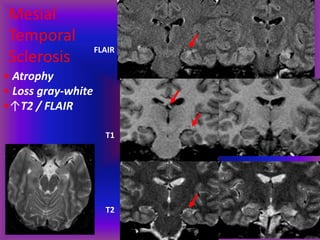

Mesial Temporal Sclerosis

Most common pathology found in

medically refractory epilepsy patients

Rare under age 10 or with new seizures

Pathogenesis unknown

- Post ictal / kindling?

Pathology:

Hippocampal atrophy / gliosis

Mesial

Temporal

Sclerosis

FLAIR

T1

T2

• Atrophy

• Loss gray-white

•↑T2 / FLAIR